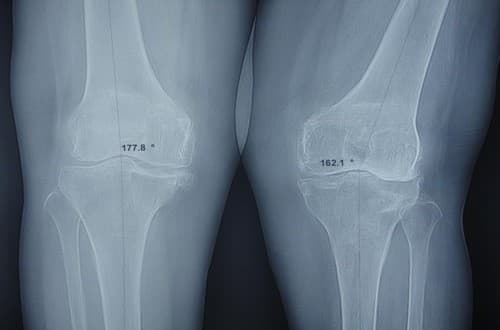

Chụp X quang đầu gối là chỉ định cần thiết trong chẩn đoán và điều trị các bệnh lý ở vùng khớp gối vậy khi nào cần chụp X quang đầu gối?

Chụp X quang khớp gối giúp chẩn đoán chính xác các bệnh lý ở khớp gối

Ngay khi có các triệu chứng bất thường ở khớp gối người bệnh cần đến bệnh viện để thực hiện chụp X quang